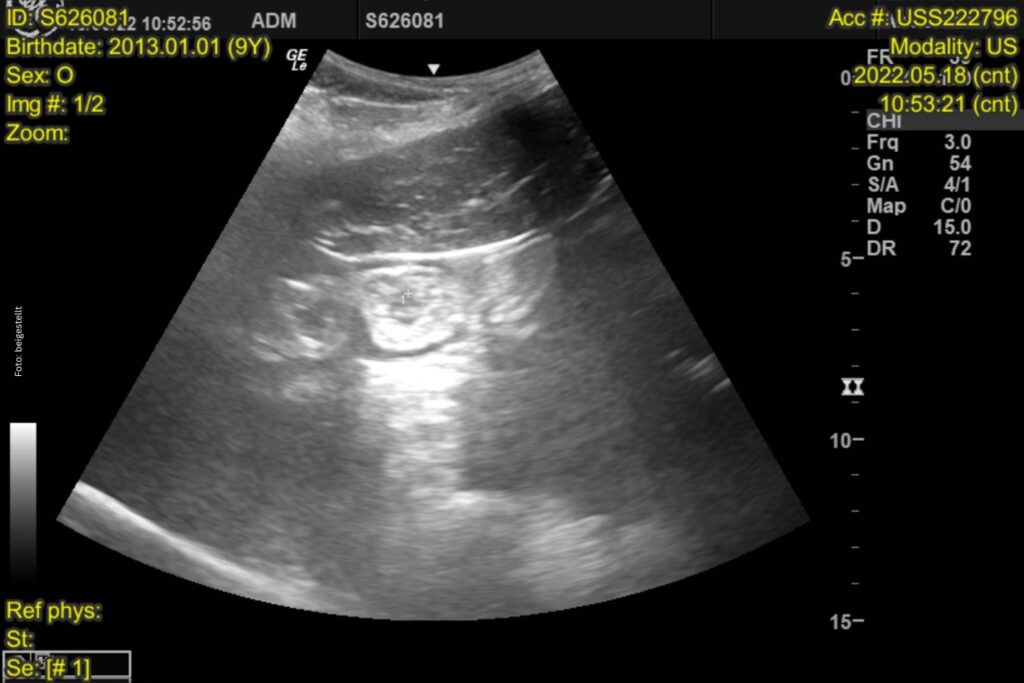

Der nächste Schritt ist ein Abdomenultraschall: Hier ist bei einer IBD eine Verdickung der Darmschleimhaut zu erwarten. Die Dünndarmschleimhaut sollte ja drei bis vier Millimeter dick sein. Ein Wert über 5,7 mm zeigt deutlich an, dass etwas nicht in Ordnung ist. Außerdem achte ich darauf, ob die Veränderungen gleichmäßig verteilt sind oder nur einzelne Darmschlingen stark verdickt sind. Ein weiterer diagnostischer Schritt ist die Abdominozentese: Hier werden das Totalprotein, die Gesamtzellzahl sowie das Laktat gemessen. Dies ist auch wichtig, um ein Lymphom, eine weitere Differentialdiagnose, ausschließen zu können, wobei hier das Bauchhöhlenpunktat auch unverändert sein kann. Bei den meisten Pferden mit IBD ist das Totalprotein nicht verändert.